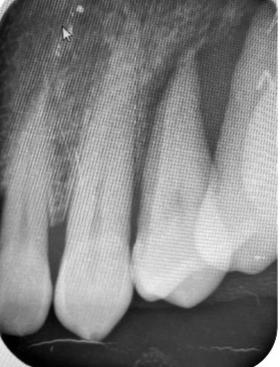

hace 8 años por lo que toma 30 mg de nifedipino cada 12 horas, amlodipino 5 mg cada 24 horas, telmisartan 40 mg cada 12 horas y metropolol 100 mg cada 12 horas, además comenta padecer diabetes mellitus tipo II desde hace 7 años por lo que también toma 50 mg de metformina cada 12 horas y dapagliflozina 10 mg cada 24 horas. Clínicamente se observó una encía roja y sangrante, profundos sondeos, una notable hiperplasia gingival, depósitos de cálculo y movilidad dental grado III en todos los órganos dentarios a excepción del segundo premolar superior derecho al canino superior izquierdo, quienes presentaban una movilidad grado II. Radiográficamente se encontró una pérdida de inserción radiográfica avanzada generalizada

en la arcada inferior, y grupos molares de ambos cuadrantes superiores (Figura 1), los únicos órganos dentarios con posibilidad de preservación en boca a través de terapia periodontal se encontraron en el sector anterior de la arcada superior anteriormente mencionados con movilidad grado II

(Figura 2). Por lo que se diagnostica con periodontitis generalizada, estado IV, grado C (Figura 3).